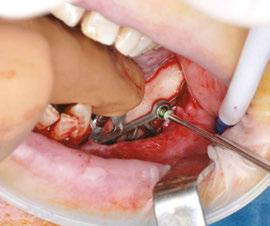

After the soft tissue is prepared, the bony surface is carefully cleaned. For easy insertion, the healing abutments are left in place, and the implant is held firmly with hemostatic forceps (Figure 7). The implant is inserted via distal translation in the direction of the angle of the mandible, then a mesio-anterior rotation. The surgeon must control the lack of mobility and the adaptation of the implant to the bony surface at all points (Figures 8A, 8B, 8C, and 8D).

To ensure the implant is stable during the osseointegration period, an osteosynthesis screw is placed in the prepared space (Figures 9A, 9B, 9C, and 9D).

Figures 8A-8D: Placing the subperiosteal implant and monitoring its adaptation Figures 5A and 5B: 5A. Initial clinical view. 5B. Access flap Figure 6: Periosteal expansion using a soft brush Figure 7: Prehension of the subperiosteal implant